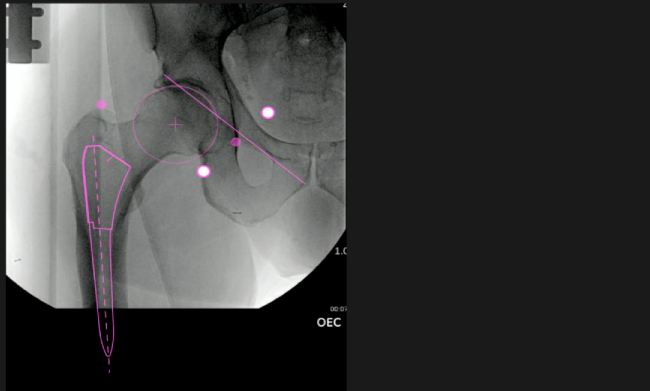

Planeación preoperatoria mediante la creación de plantillas digitales para reemplazo de cadera y análisis intraoperatorio

Mayor nivel de información intraoperatoria facilita la colocación correcta de los implantes:

Inclinación y anteversión de la copa acetabular para una correcta colocación del implante.

Desplazamiento y offset para posicionamiento óptimo del componente (vástago) femoral.